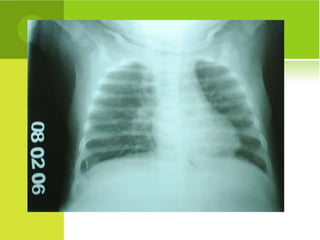

CAUSAS DE SIBILÂNCIAEM LACTENTES TORO, AADC; RIBEIRO, JD. Síndrome do Lactente Sibilante. In: Doenças Respiratórias, FMUSP, 2008 Frequentes Menos Frequentes Raras Bonquiolite viral aguda Asma atópica Infecções virais Doença do RGE Outras síndromes aspirativas Corpo estranho DBP Insuf. Cardíaca Tuberculose Imunodeficiência Fibrose cística Anel vascular Fístula traqueo-esofágica Bronquiolite obliterante Traqueomalácia Tumores mediastinais